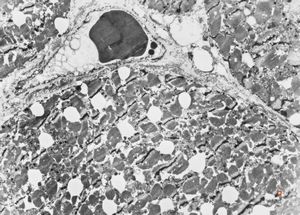

M, 7w. | mitochondrial cardiomyopathy - semithin section(arrows - megamitochondria)

M, 7w. | mitochondrial cardiomyopathy (N - nucleus, M - megamitochondria,R - dilated endoplasmic reticulum)- autopsy sample